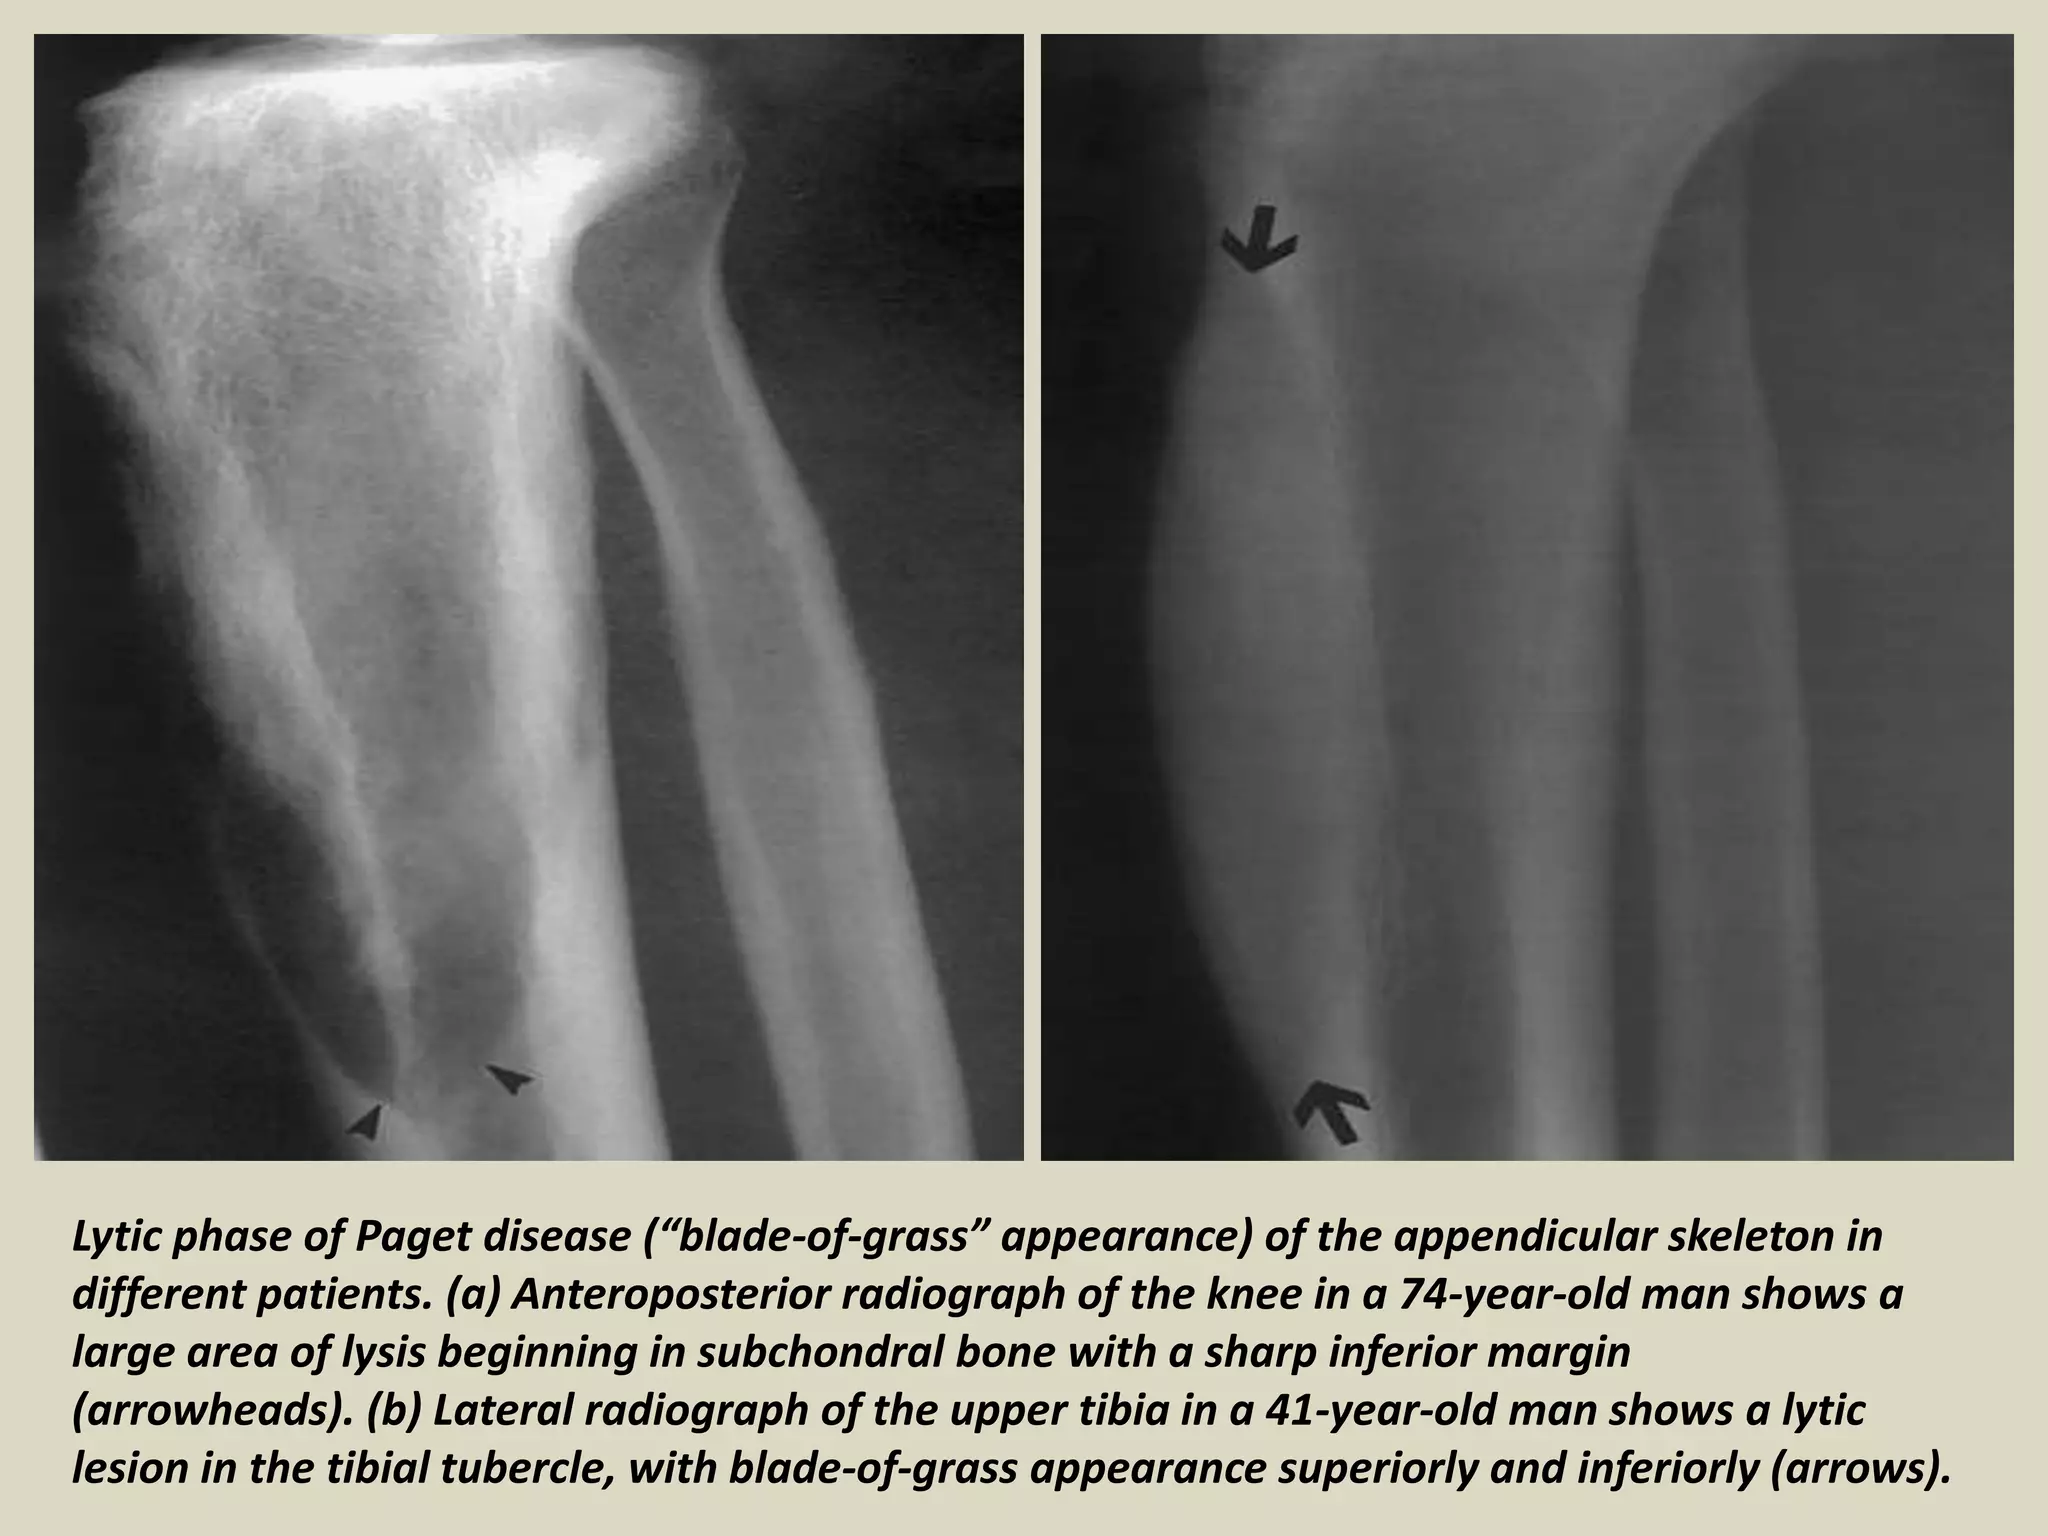

Lytic phase of Paget disease (“blade-of-grass” appearance) of the appendicular skeleton in

different patients. (a) Anteroposterior radiograph of the knee in a 74-year-old man shows a

large area of lysis beginning in subchondral bone with a sharp inferior margin

(arrowheads). (b) Lateral radiograph of the upper tibia in a 41-year-old man shows a lytic

lesion in the tibial tubercle, with blade-of-grass appearance superiorly and inferiorly (arrows).